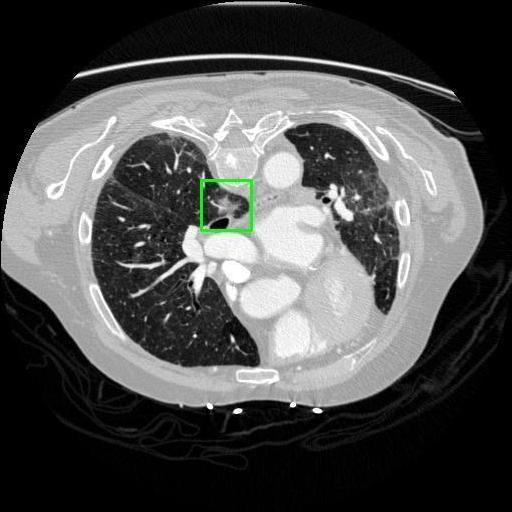

We developed an AI-based system using deep learning models for analyzing lung CT scans to detect and classify pulmonary nodules. We chose the YOLOv11 architecture for its enhanced object detection capability and adapted it specifically for medical imaging, incorporating pixel-level precision and severity classification.

Classification into three severity levels with colored bounding boxes.

Successfully built and deployed an AI model (YOLOv11) capable of detecting lung nodules in CT scans with high accuracy and real-time performance.

Designed a severity classification system that categorizes nodules into null, moderate, and severe using colored bounding boxes, assisting in rapid clinical decision-making.